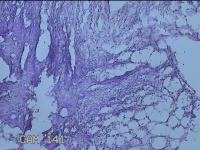

右侧会阴部结节

性别

女

年龄

31岁

临床诊断

皮脂腺囊肿

一般病史

发现右侧会阴部结节2个月。

标本名称

大体所见

灰白暗红色结节1.7x1.3x0.3cm一个,表面糜烂,切开结节呈实性,切面灰白暗红色,质软。

图3

炎症性病变。